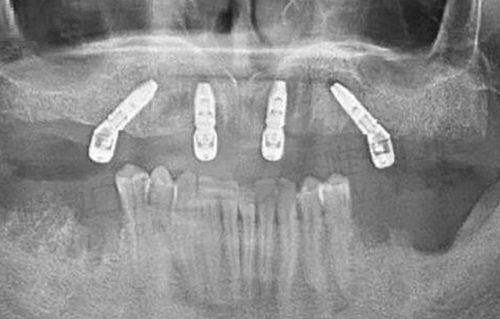

医生都是有着十多年甚至二十多年临床经验的靠谱选手,擅长种植牙、正畸矫正、牙齿美容、龋齿治疗等项目。有时候还会有四川省口腔医院的骨干医生联合坐诊,特别对于牙列缺失、全口种植类来说,更加专精且成功几率高。